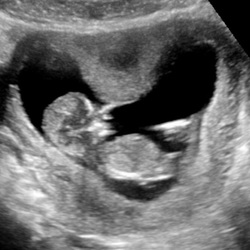

Woensdag onze eerste echo, super spannend en heel veel zin in!